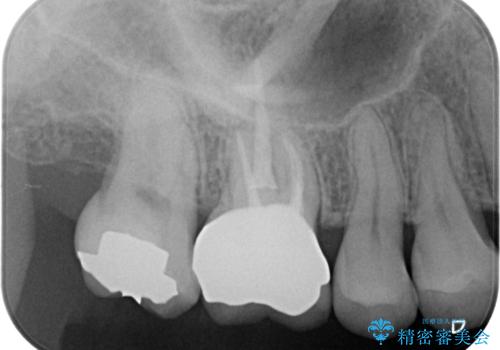

セラミックのインレーでは強度に不安が残るため、セラミッククラウンで全体を被覆することとしました。

- 右上6:仮歯+ジルコニアクラウン/11,000円+110,000円費用は治療当時の料金となります

セラミックは劣化で変色することがありません。

表面も滑沢で汚れが付着しにくく、適合の良いセラミッククラウンは治療後の虫歯リスクを抑えてくれます。